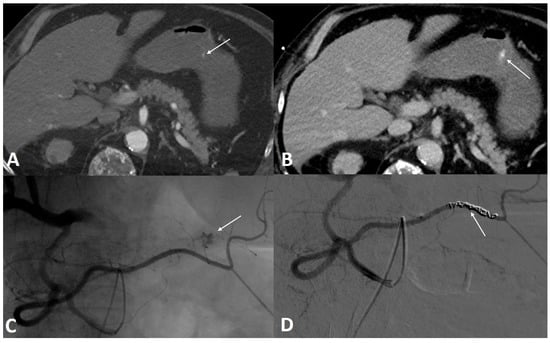

2.4. Transarterial Embolization Methods and Techniques

3.4. Post-Angiography Course